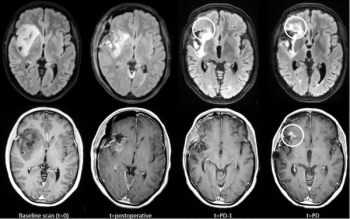

In a comparison of contrast-enhanced T1-weighted (CET1w) MRI (and T2-weighted MRI/FLAIR imaging, researchers found that only three out of 82 cases of glioma progression were solely detected with CET1w MRI.